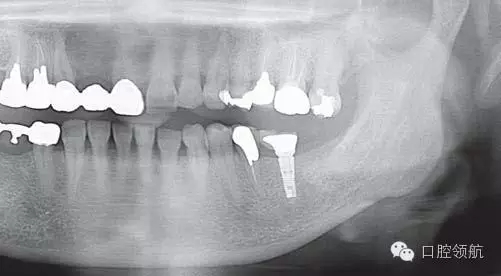

全景X線片上沒(méi)發(fā)現(xiàn)有骨吸收現(xiàn)象(圖2),發(fā)現(xiàn)在MGJ附近和種植體周?chē)l溝里有白色顆粒的存在(圖3)。

圖2 當(dāng)日的全景X線片上沒(méi)發(fā)現(xiàn)有骨吸收現(xiàn)象。